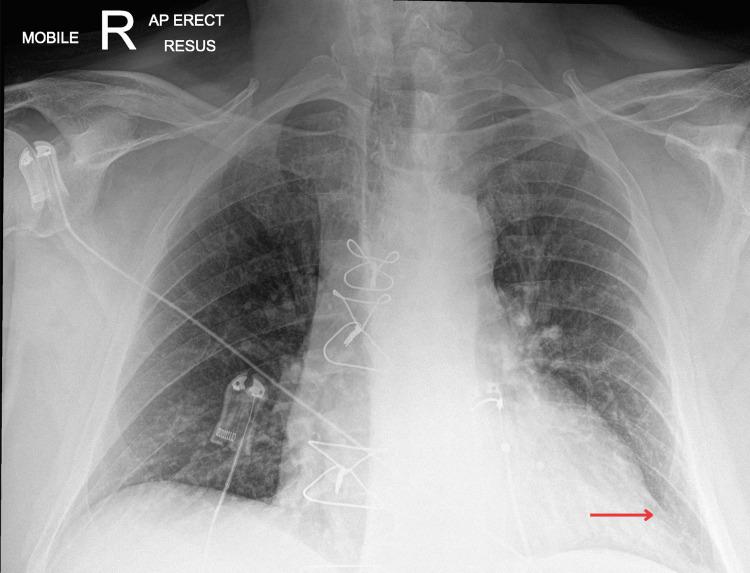

人工瓣膜心内膜炎与主动脉根部脓肿:一例高风险感染病例

Prosthetic Valve Endocarditis and Aortic Root Abscess: A Case of High-Risk Infection.

Aortic root abscess is a severe complication of infective endocarditis (IE), particularly in patients with prosthetic valves, nearly doubling mortality risk. Due to the potential for rupture and systemic spread, urgent surgical intervention is recommended. We present the case of a 77-year-old man with a recent aortic valve replacement and a history of discitis who presented with non-specific symptoms, complete heart block, and persistent bacteremia. Multimodal imaging, including positron emission tomography (PET) and CT coronary angiography, confirmed an aortic root abscess. Following the IE multidisciplinary team (MDT) recommendations, the patient underwent successful aortic valve and root repair. Post-operatively, he required a pacemaker and dual antibiotic therapy for eight weeks, with no further infection detected. This case highlights the diagnostic challenges of prosthetic valve endocarditis, the critical role of multimodal imaging in detecting complications, and the necessity of early surgical intervention. The development of a heart block underscores the impact of aortic root abscess on conduction pathways. MDT management was essential in optimising patient outcomes.

摘要

主动脉根部脓肿是感染性心内膜炎(IE)的一种严重并发症,尤其在人工瓣膜置换患者中,死亡风险几乎翻倍。由于存在破裂和全身扩散的可能性,建议进行紧急手术干预。我们报告一例77岁男性病例,该患者近期接受主动脉瓣置换术,有椎间盘炎病史,表现为非特异性症状、完全性心脏传导阻滞和持续性菌血症。包括正电子发射断层扫描(PET)和CT冠状动脉造影在内的多模态成像证实了主动脉根部脓肿。按照IE多学科团队(MDT)的建议,患者成功接受了主动脉瓣和根部修复手术。术后,他需要起搏器和为期八周的双联抗生素治疗,未检测到进一步感染。该病例凸显了人工瓣膜心内膜炎的诊断挑战、多模态成像在检测并发症中的关键作用以及早期手术干预的必要性。心脏传导阻滞的出现强调了主动脉根部脓肿对传导通路的影响。MDT管理对于优化患者预后至关重要。